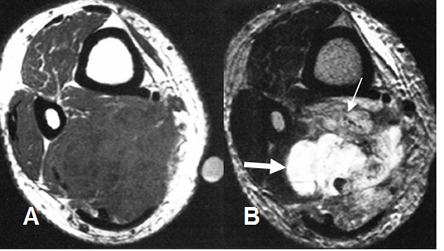

Fig 110 A. Sarcoma pleomórfico indiferenciado.

A: RM axial en T1. Lesión hipointensa y heterogénea de tejidos blandos y crecimiento agresivo, en el compartimiento posterior de la pierna.

B: RM axial en T2. Imagen heterogénea con área de señal intermedia por contenido fibroso (Flecha delgada) y otra hiperintensa, por necrosis. (Flecha gruesa).